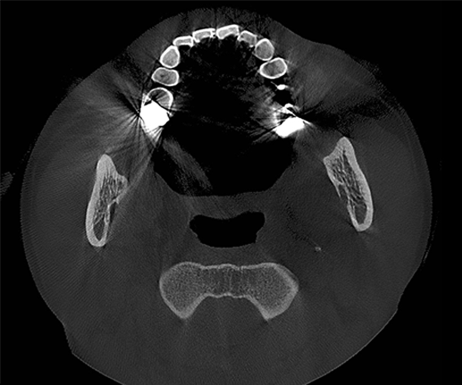

T-MAR Metal Artifact Reduction

T-MAR Metal Artifact Reduction in LargeV Dental CBCT

With the new T-MAR module, the system automatically removes metal artifacts and corrects image distortions intelligently.

Hence, the final images remain clear, accurate, and clinically reliable.